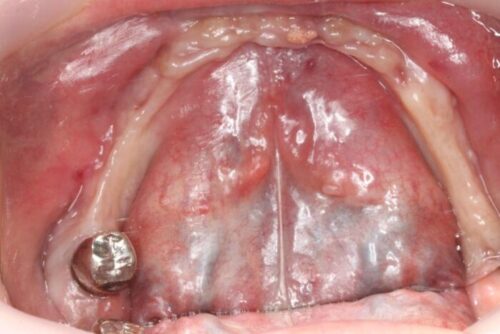

さて今回は、下顎のインプラント治療の症例を紹介します。

【治療前】

【治療後】

| 治療内容 | 下顎のインプラント治療 |

| 治療期間 | 6ヶ月 |

| 治療費用 | 250万円( 税抜 ) |

| 副作用・リスク | 外科処置が伴うため、術後の疼痛・腫脹・出血・咬合痛などを生じる事があります。 麻酔を行う場合、腫れやむくみを生じる事があります。 また、被せ物や土台が外れたり、欠けたり、緩んだりする事があります。 |